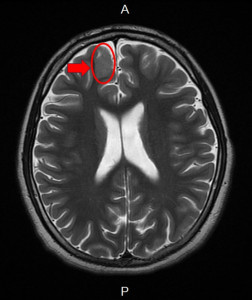

治療椎間盤突出 脊椎微創內視鏡手術復原快

21歲男大生,搬東西後突然屁股產生劇痛,一路從大腿痛到小腿,痛不欲生,腰都直不起來,生活品質大受影響,整天只能躺在床上,翻身都很痛苦,經人介紹至台大竹東骨科黃鼎鈞醫師門診診治,核磁共振及神經...